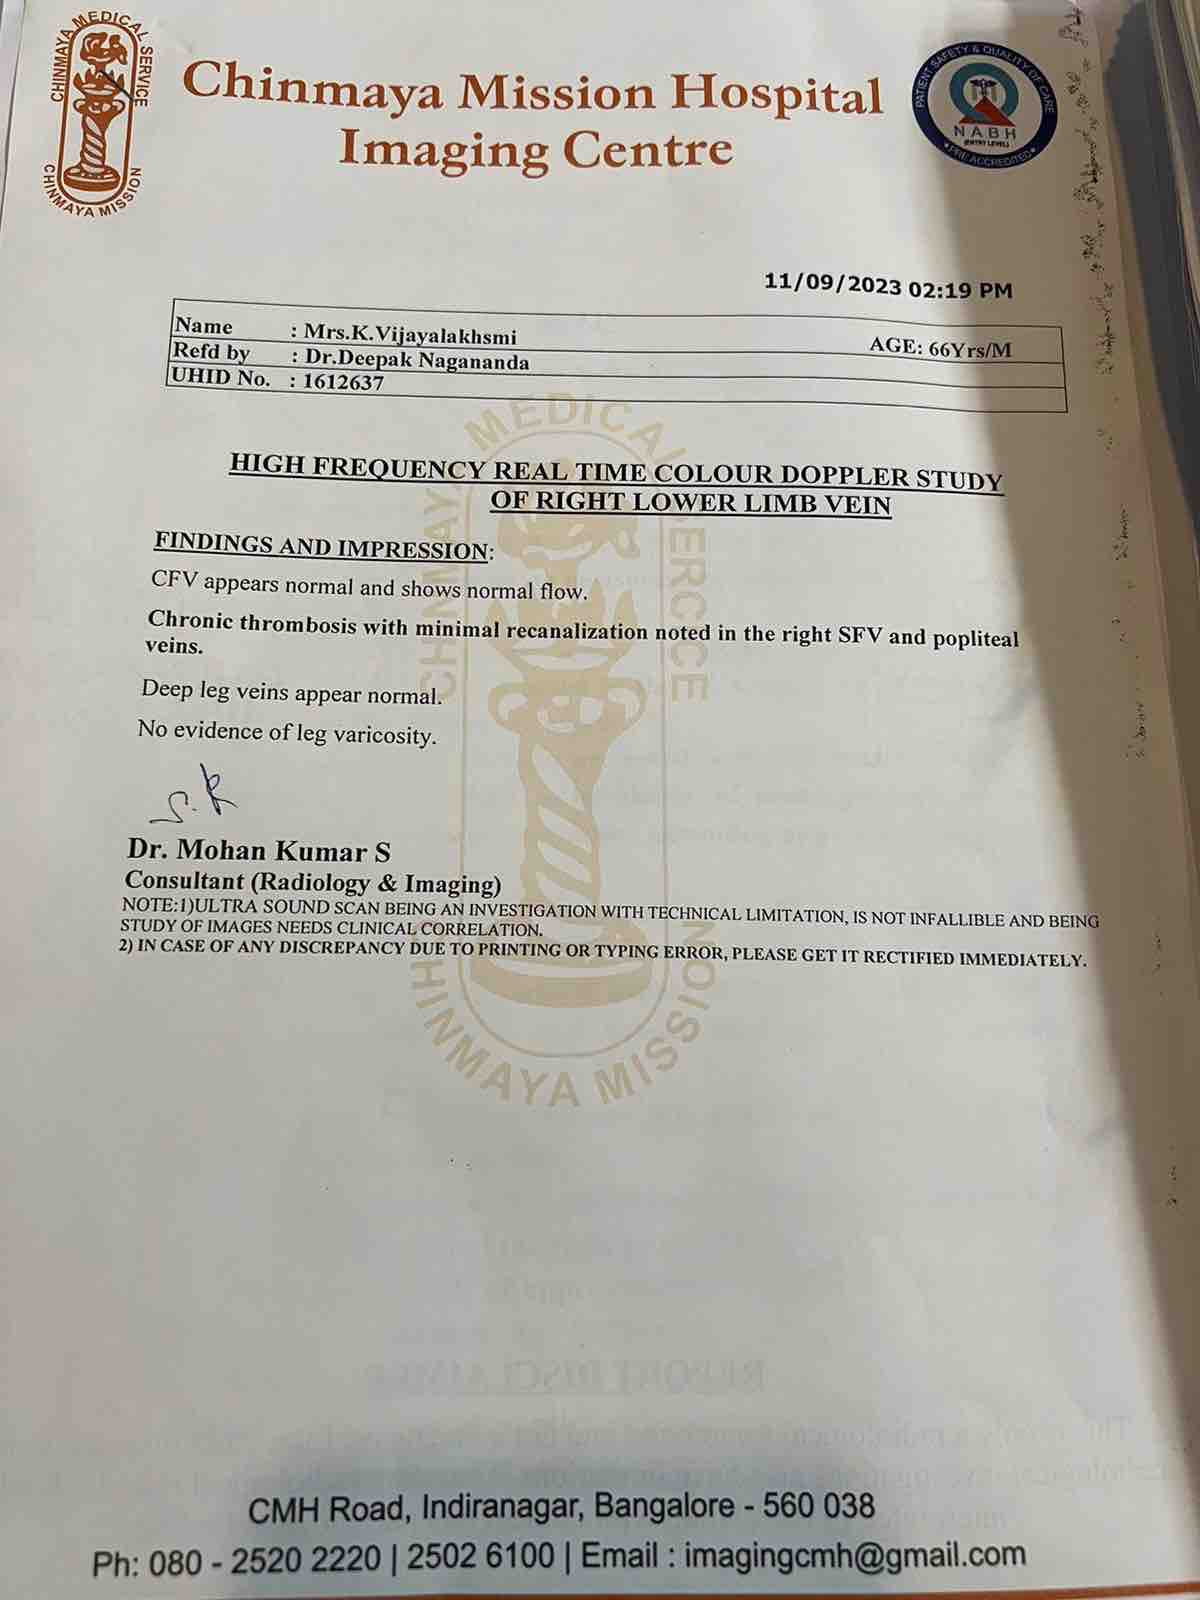

We are reaching out to you today with a heavy heart and a plea for help. Our beloved 66-year-old mother K VIJYA LAKSHMI, has been facing an incredibly challenging journey since 16th May when she had brain stroke & underwent emergency brain and abdomen surgery. Her recovery has been a rollercoaster of ups and downs.

During her hospitalization, she endured multiple complications, including respiratory distress, recurrent severe infections, and even seizure-like activity. Through it all, she has shown immense strength and determination. Still she require three more surgeries to stand on the path of recovery.